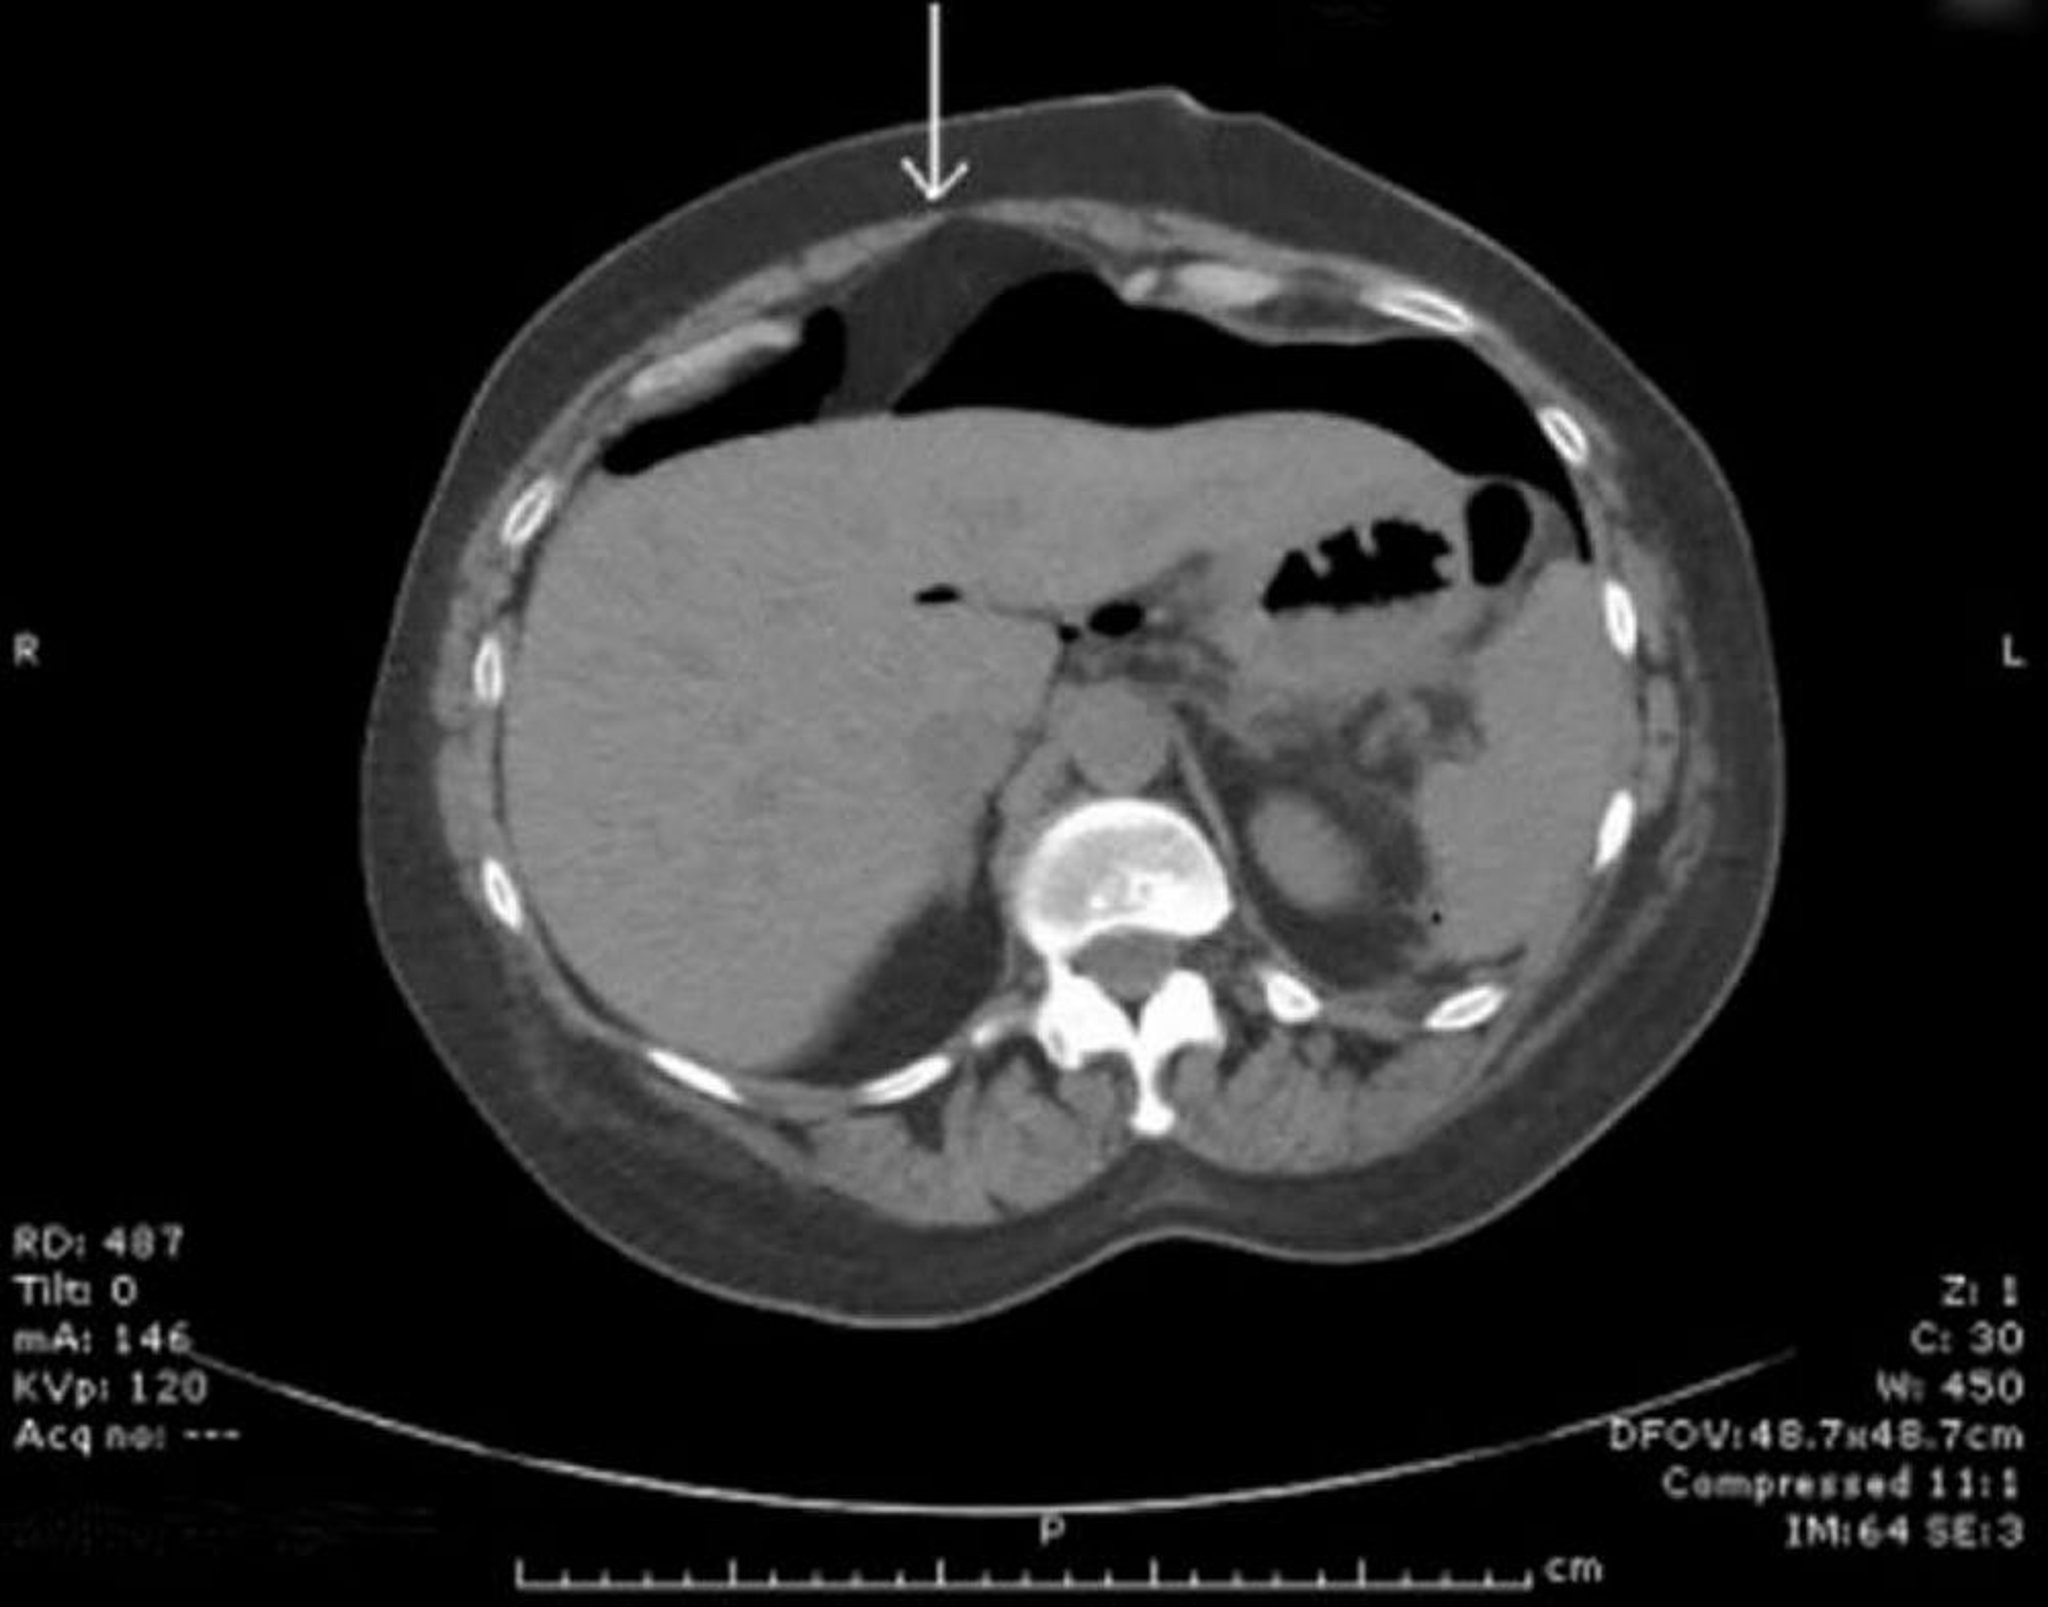

TC con aire peritoneal libre

El aire libre se observa por delante del hígado. La flecha señala el ligamento falciforme.